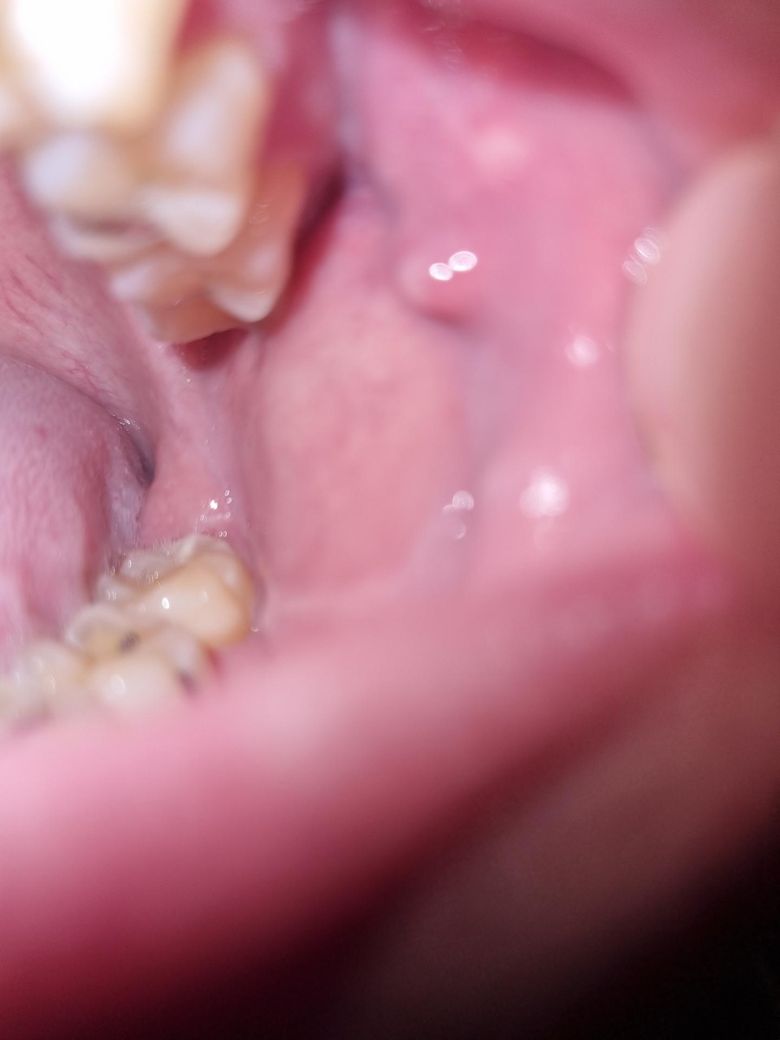

볼 양쪽에 뭐가 생겼습니다.궁금하네요

양쪽으로 위쪽에 돌기같은게 생겼는데 뭔가요??

사진으로 보이는 현상은 점막 조직이 치아에 눌려서 생기는 압흔입니다. 치아에 가해지는 힘이 너무 강하다면 해당 부위가 치아 사이로 밀려나면서 치아의 모양이 찍혀나오는 것입니다.

사진에 보이는건 볼살이 치아에 씹혀서 생긴겁니다. 크게 문제가 되는건 없으니 크게 걱정하지마세요.

해당 부분은 정상적인 구조물로 구강 내에 존재하는 침샘 중 하나입니다. 잇몸 상태에 따라서 두드러지게 보일 수 있고 묻혀서 보이지 않을 수 있습니다. 정상적인 구강 내 조직이므로 크게 걱정하지 않으셔도 됩니다.

볼을 씹는 등 자극에 의해서 생긴 섬유성 조직 같습니다. 특별히 악성 종양의 양상은 아니니 너무 걱정은 안하셔도 되겠습니다.